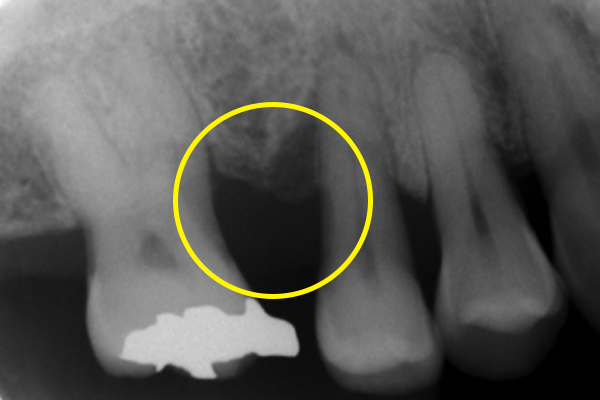

また、日本国内で一般的に行われる歯周病における抜歯の判断基準は、比較的すぐに「抜歯」と判断する傾向があります。歯周病専門医として、世界基準に沿った抜歯の判断をし、残せると判断すれば、全力を尽くして歯を残す治療を行います。

どうしても、抜歯が必要な場合も、抜歯する歯は最小限に抑え、噛む機能を最大限に維持していきます。